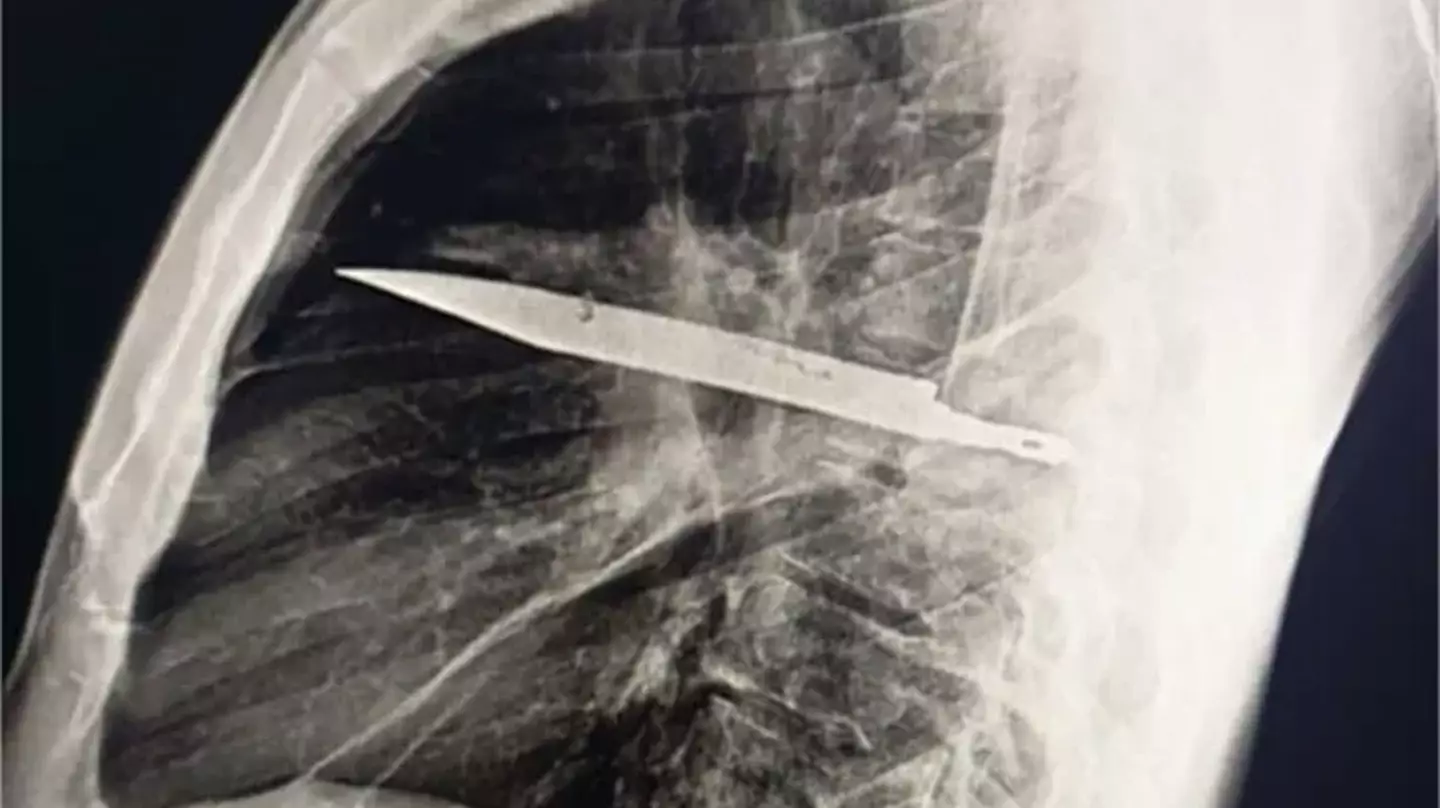

Sometimes truth is stranger than fiction, after an X-ray revealed the man had a sizeable knife buried deep inside his chest.

After ordering an X-ray, a 'retained metallic object' was found, and medics realised it was a knife, and it was surrounded by 'pus and necrotic tissue'.

It had entered his body through his right shoulder.